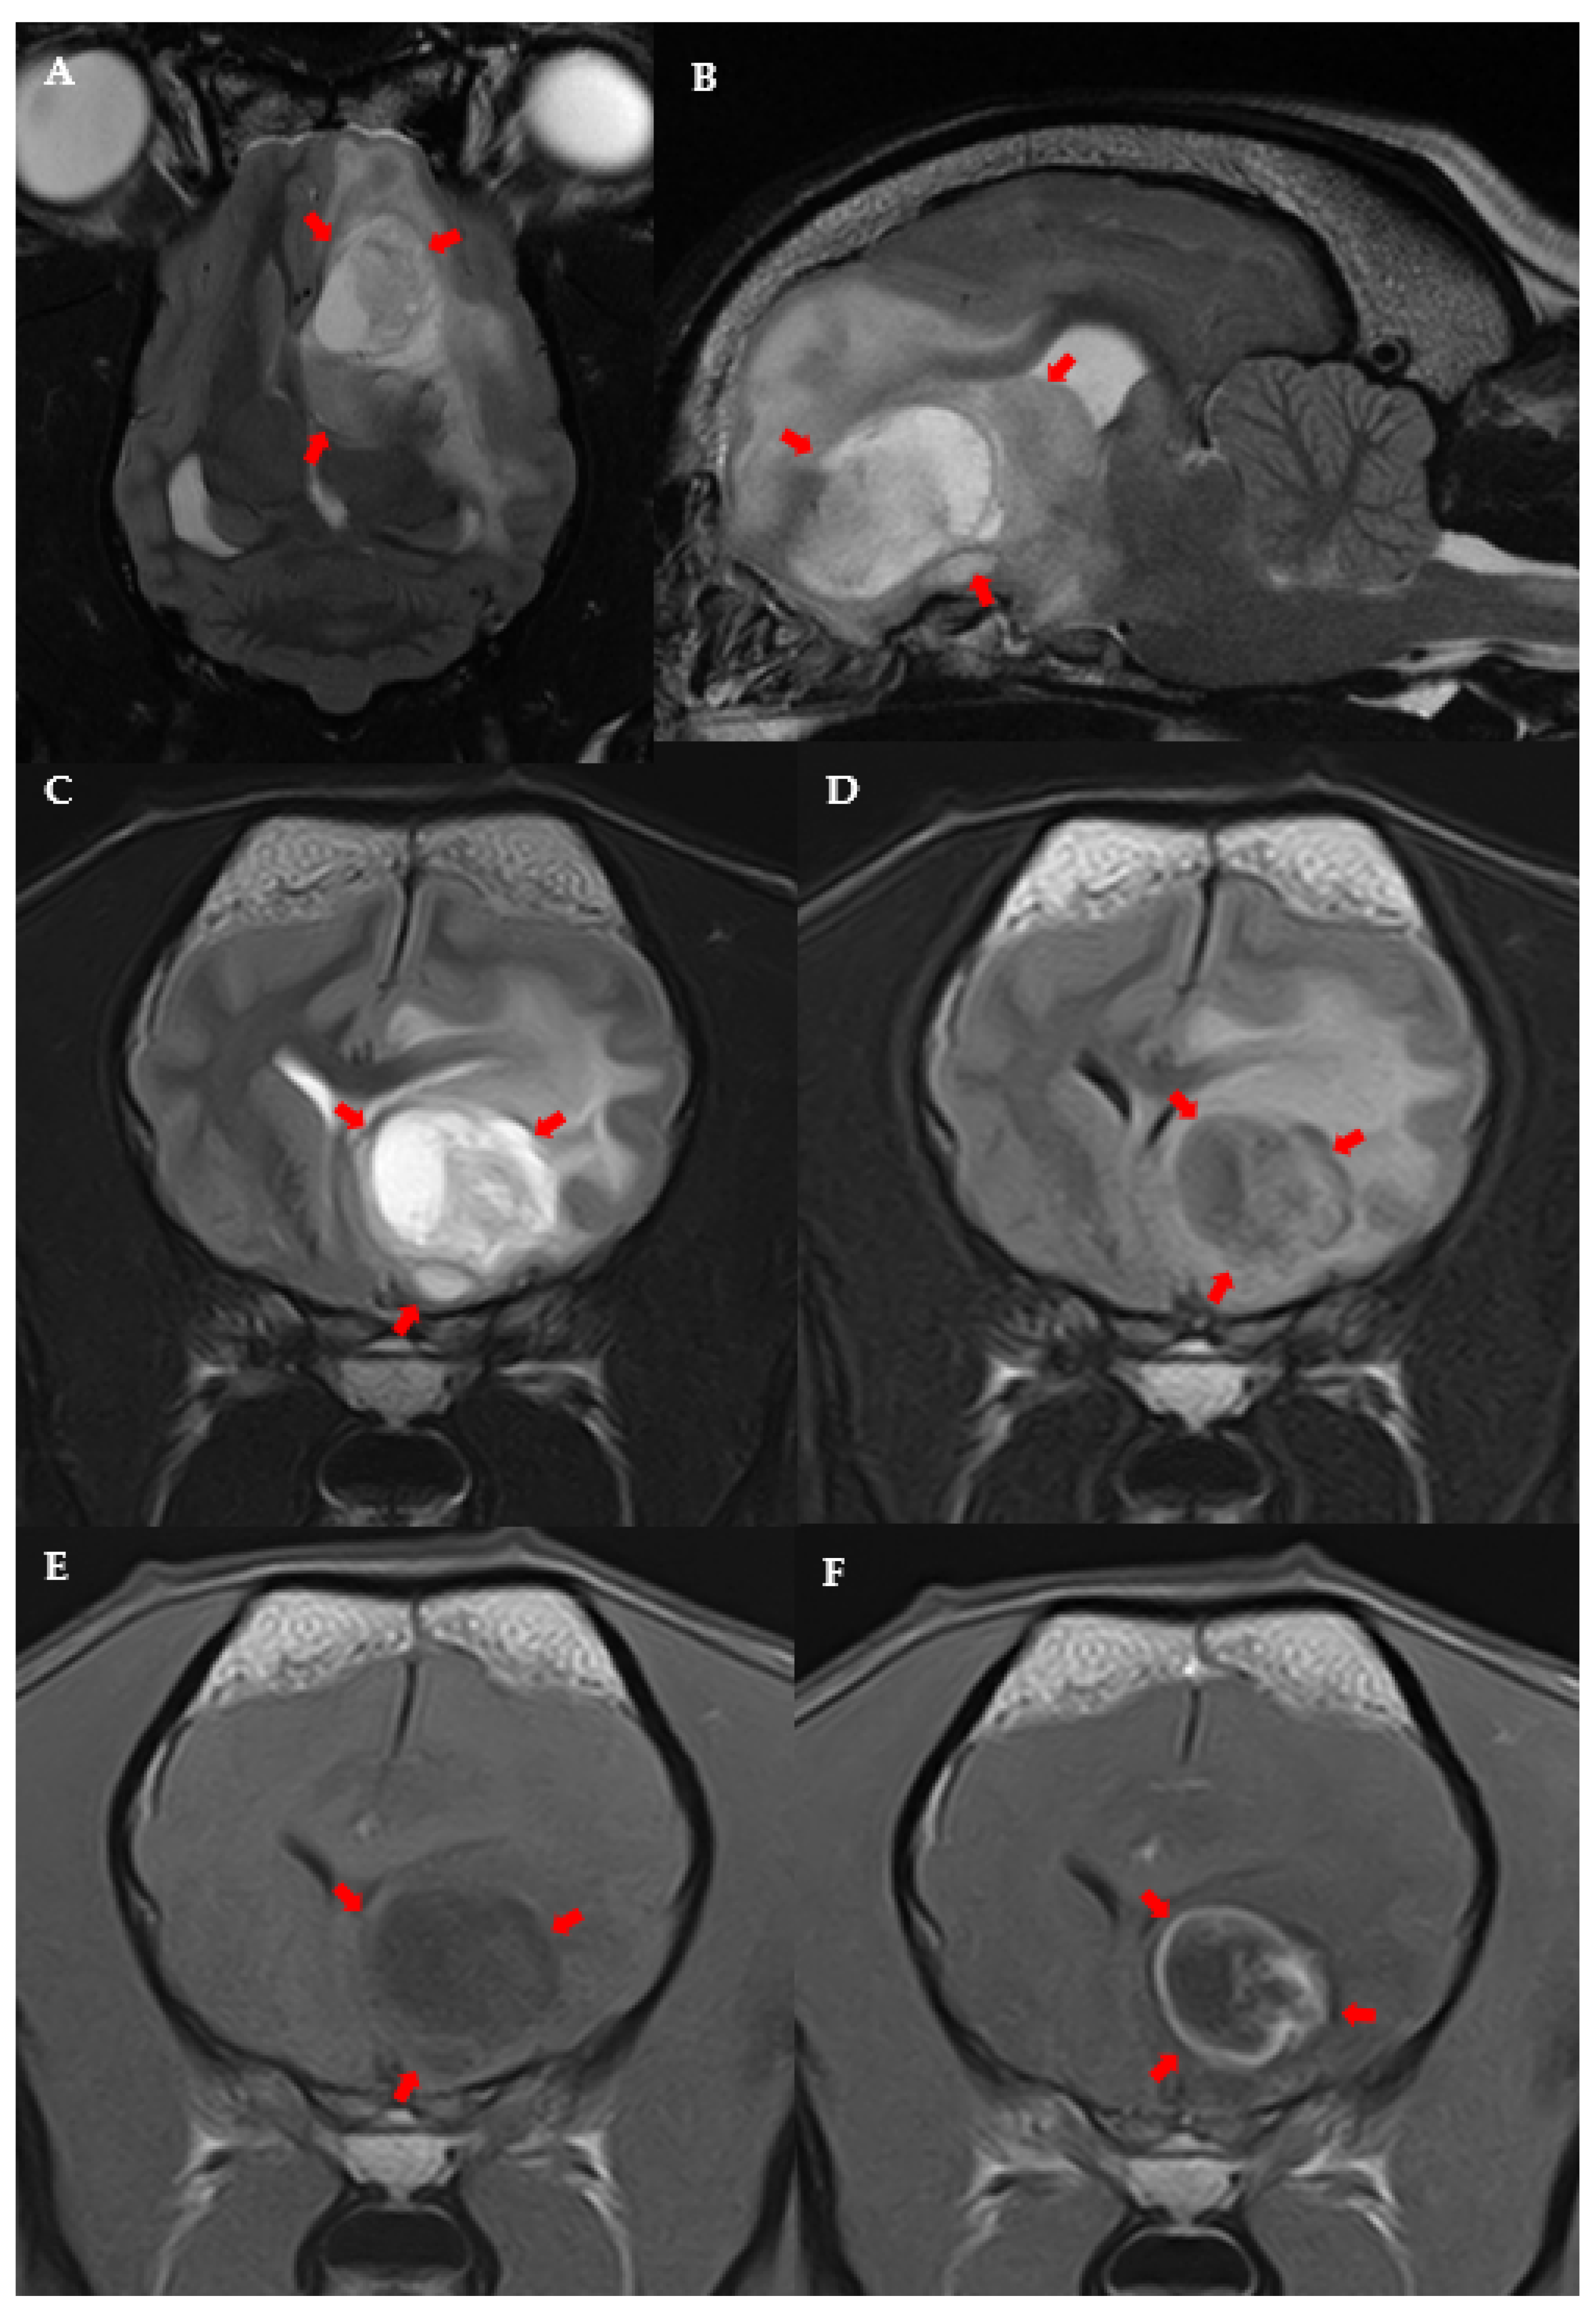

From onlinelibrary.wiley.com

Treatment of MRI‐Diagnosed Trigeminal Peripheral Nerve Sheath Tumors by Stereotactic Mri Anatomy Dog in the last few years, anatomical and functional magnetic resonance imaging (mri) studies of awake. For everyone who needs to learn (or relearn) imaging neuroanatomy , there is an excellent new. this web site presents mri images of the canine head, neck, thorax, abdomen, & pelvis, viewable in transverse, sagittal & dorsal. mri brain atlas. this. Mri Anatomy Dog.